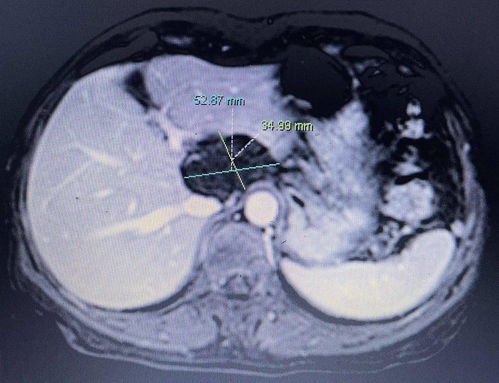

一、异常肿块或硬结

你有没有在你的身体某些部位,如乳房、颈部或腋下,摸到质地坚硬、边界模糊且活动度差的肿块?如果这些肿块持续增大且不退去,比如乳腺癌早期就可能表现为无痛性单发肿块,表面不光滑,这时应当引起你的高度警觉。